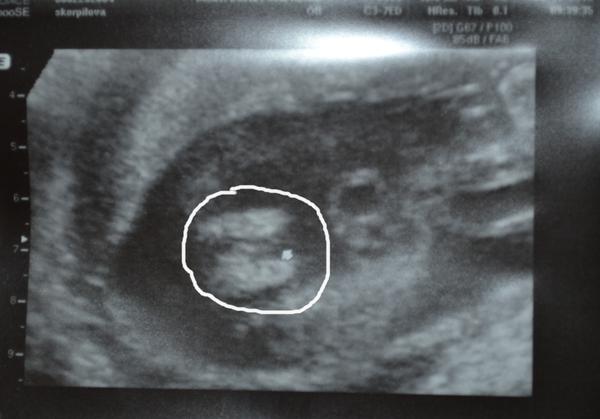

Je to holčička nebo chlapeček? Foto ultrazvuku

@antihorde mám tady jen dvě fotky z utz a to tyto.No a ani jedna není stoprocentní holka či kluk.

Tohle bylo ve 13tt a pak se mimčo stydělo pokaždé,co jsem byla na UZ.Teď ve 26tt mi můj gyndař řekl,že to vypadá spíše na holku.Že si není jistý,ale že to tak vypadá.Tak fakt nevím,už jsem se sířila s chlapečkem,ale zase jsem četla o tom,že ve 13tt mimčo nemá ještě vyvinuté pohlaví,že holčička i kluk vypadají stejně.Pohlaví je prý pořádně rozpoznat mezi 15tt-16tt,jenže to už jsme začali mít malýho stydlínka ☹.

mně přijde, že spíš holčička - říkají, že v tomto týdnu holčičkám směřuje pohlavní hrbolek dolů a chlapcům nahoru (30 stupňů).. koukněte sem: http://baby2see.com/gender/external_genitals.html